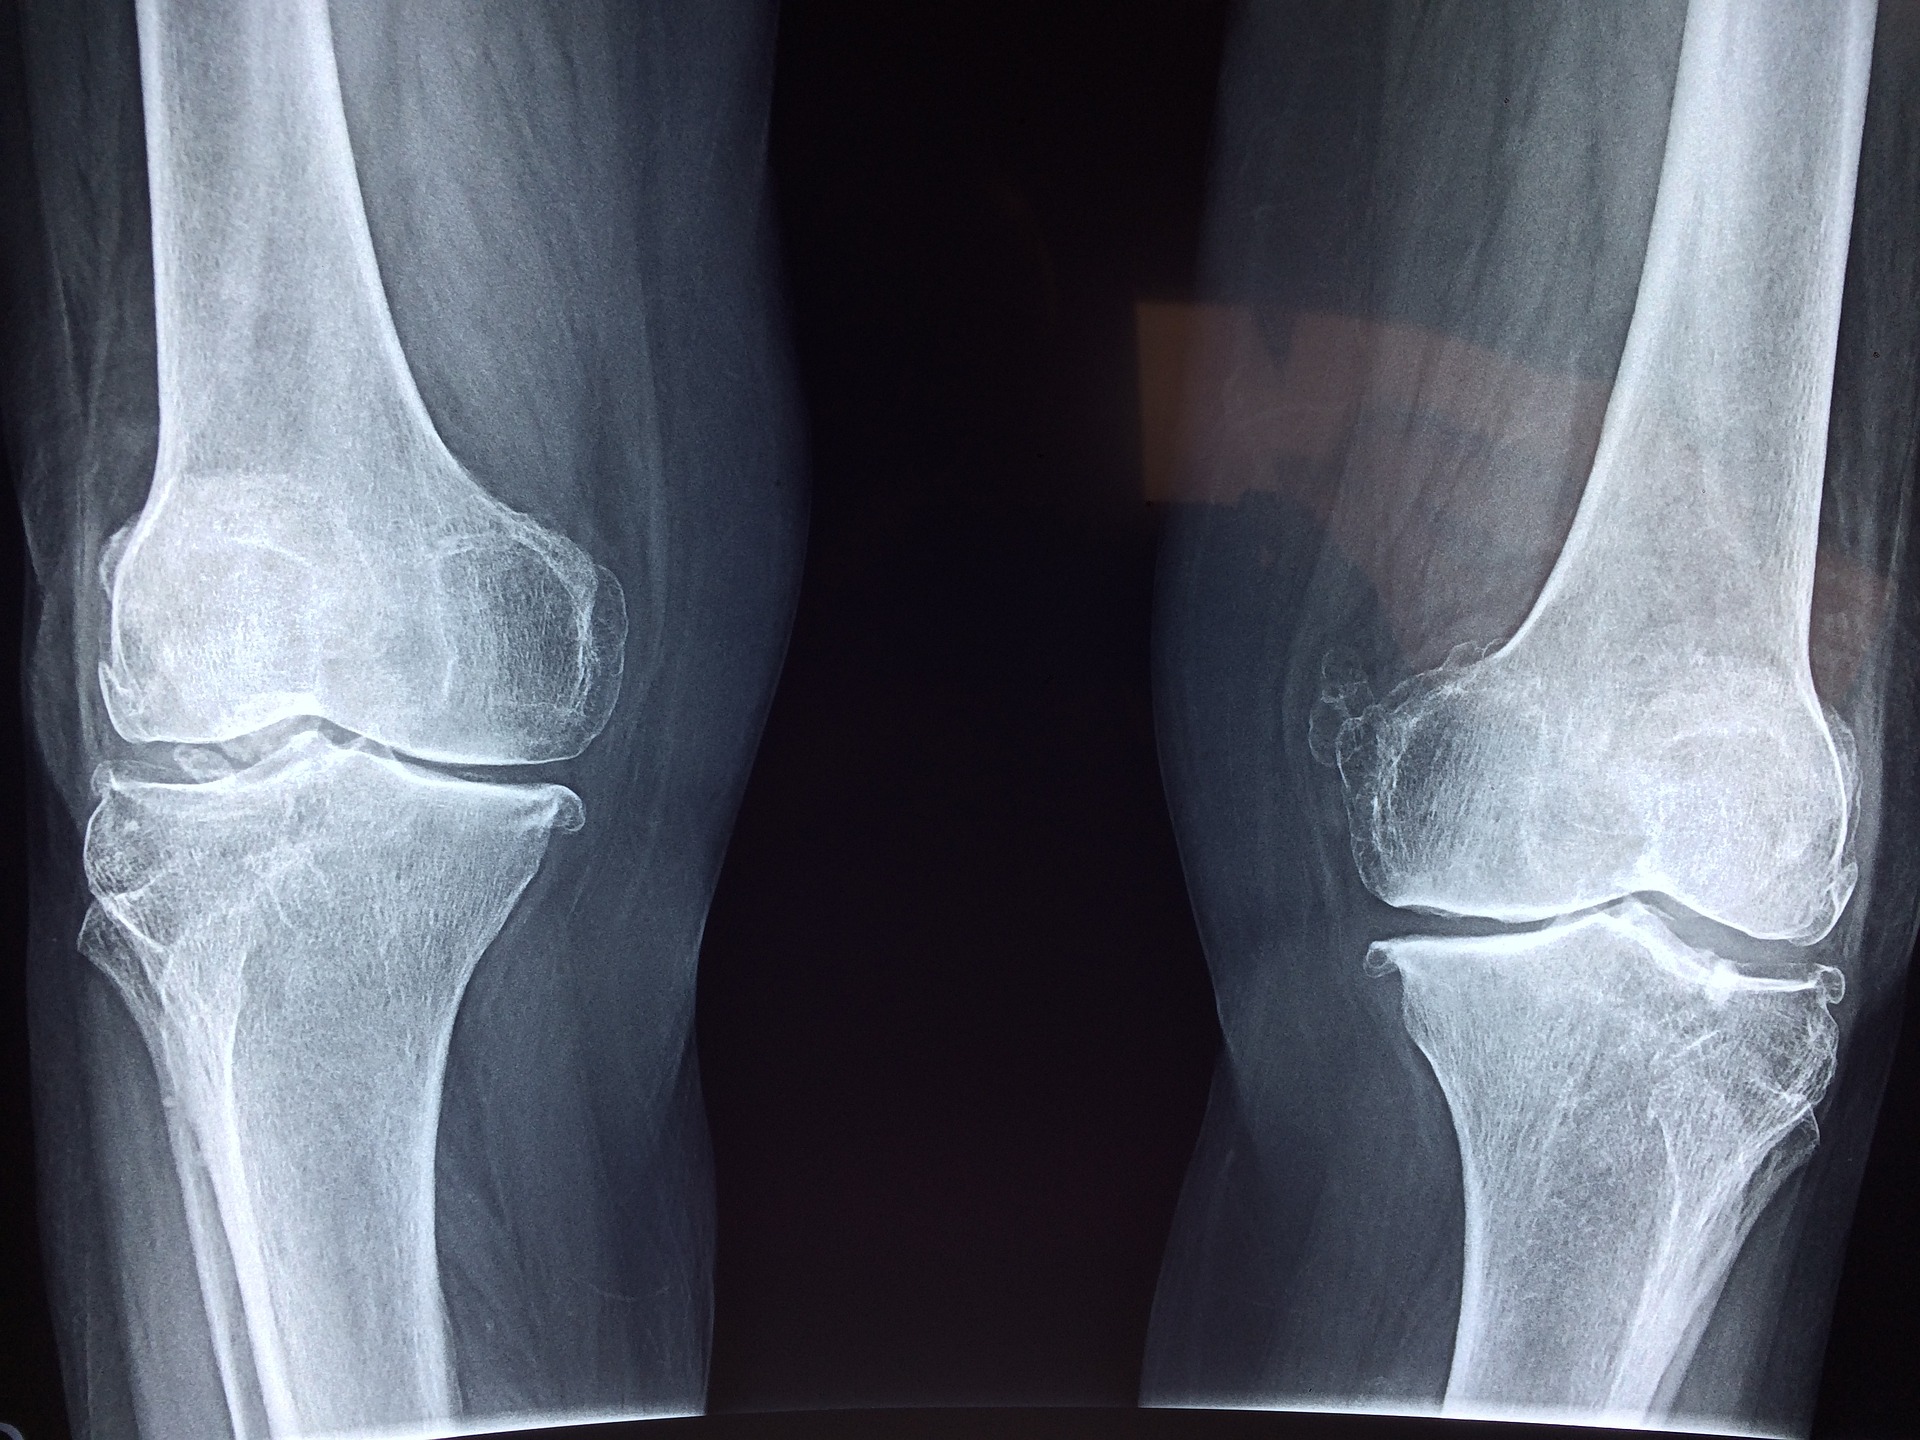

연골 손상과 퇴행성 관절염은 우리 몸의 건강한 기능을 방해하는 질환입니다. 연골은 신체적인 부담 및 나이로 인해 손상이 발생할 수 있는데, 이러한 손상은 상대적으로 긴 시간 동안 진행되며, 적극적으로 예방 조치를 취하지 않는다면 연골의 손상이 계속 진행되어 퇴행성 관절염으로 진행되게 됩니다.

저분자 콜라겐 펩타이드는 이러한 연골 손상 및 퇴행성 관절염 예방 및 개선에 도움을 줄 수 있는 방법 중 하나입니다. 저분자 콜라겐 펩타이드는 피부, 연골, 뼈, 인대, 힘줄 등에 도움을 주는 다양한 기능을 가진 단백질입니다. 이중에서도 연골의 건강을 유지하는데 중요한 역할을 합니다. 저분자 콜라겐 펩타이드는 연골의 형성과 성장을 지원하며 노화 및 관절염을 방지하는 두 가지 방식으로 작용합니다.